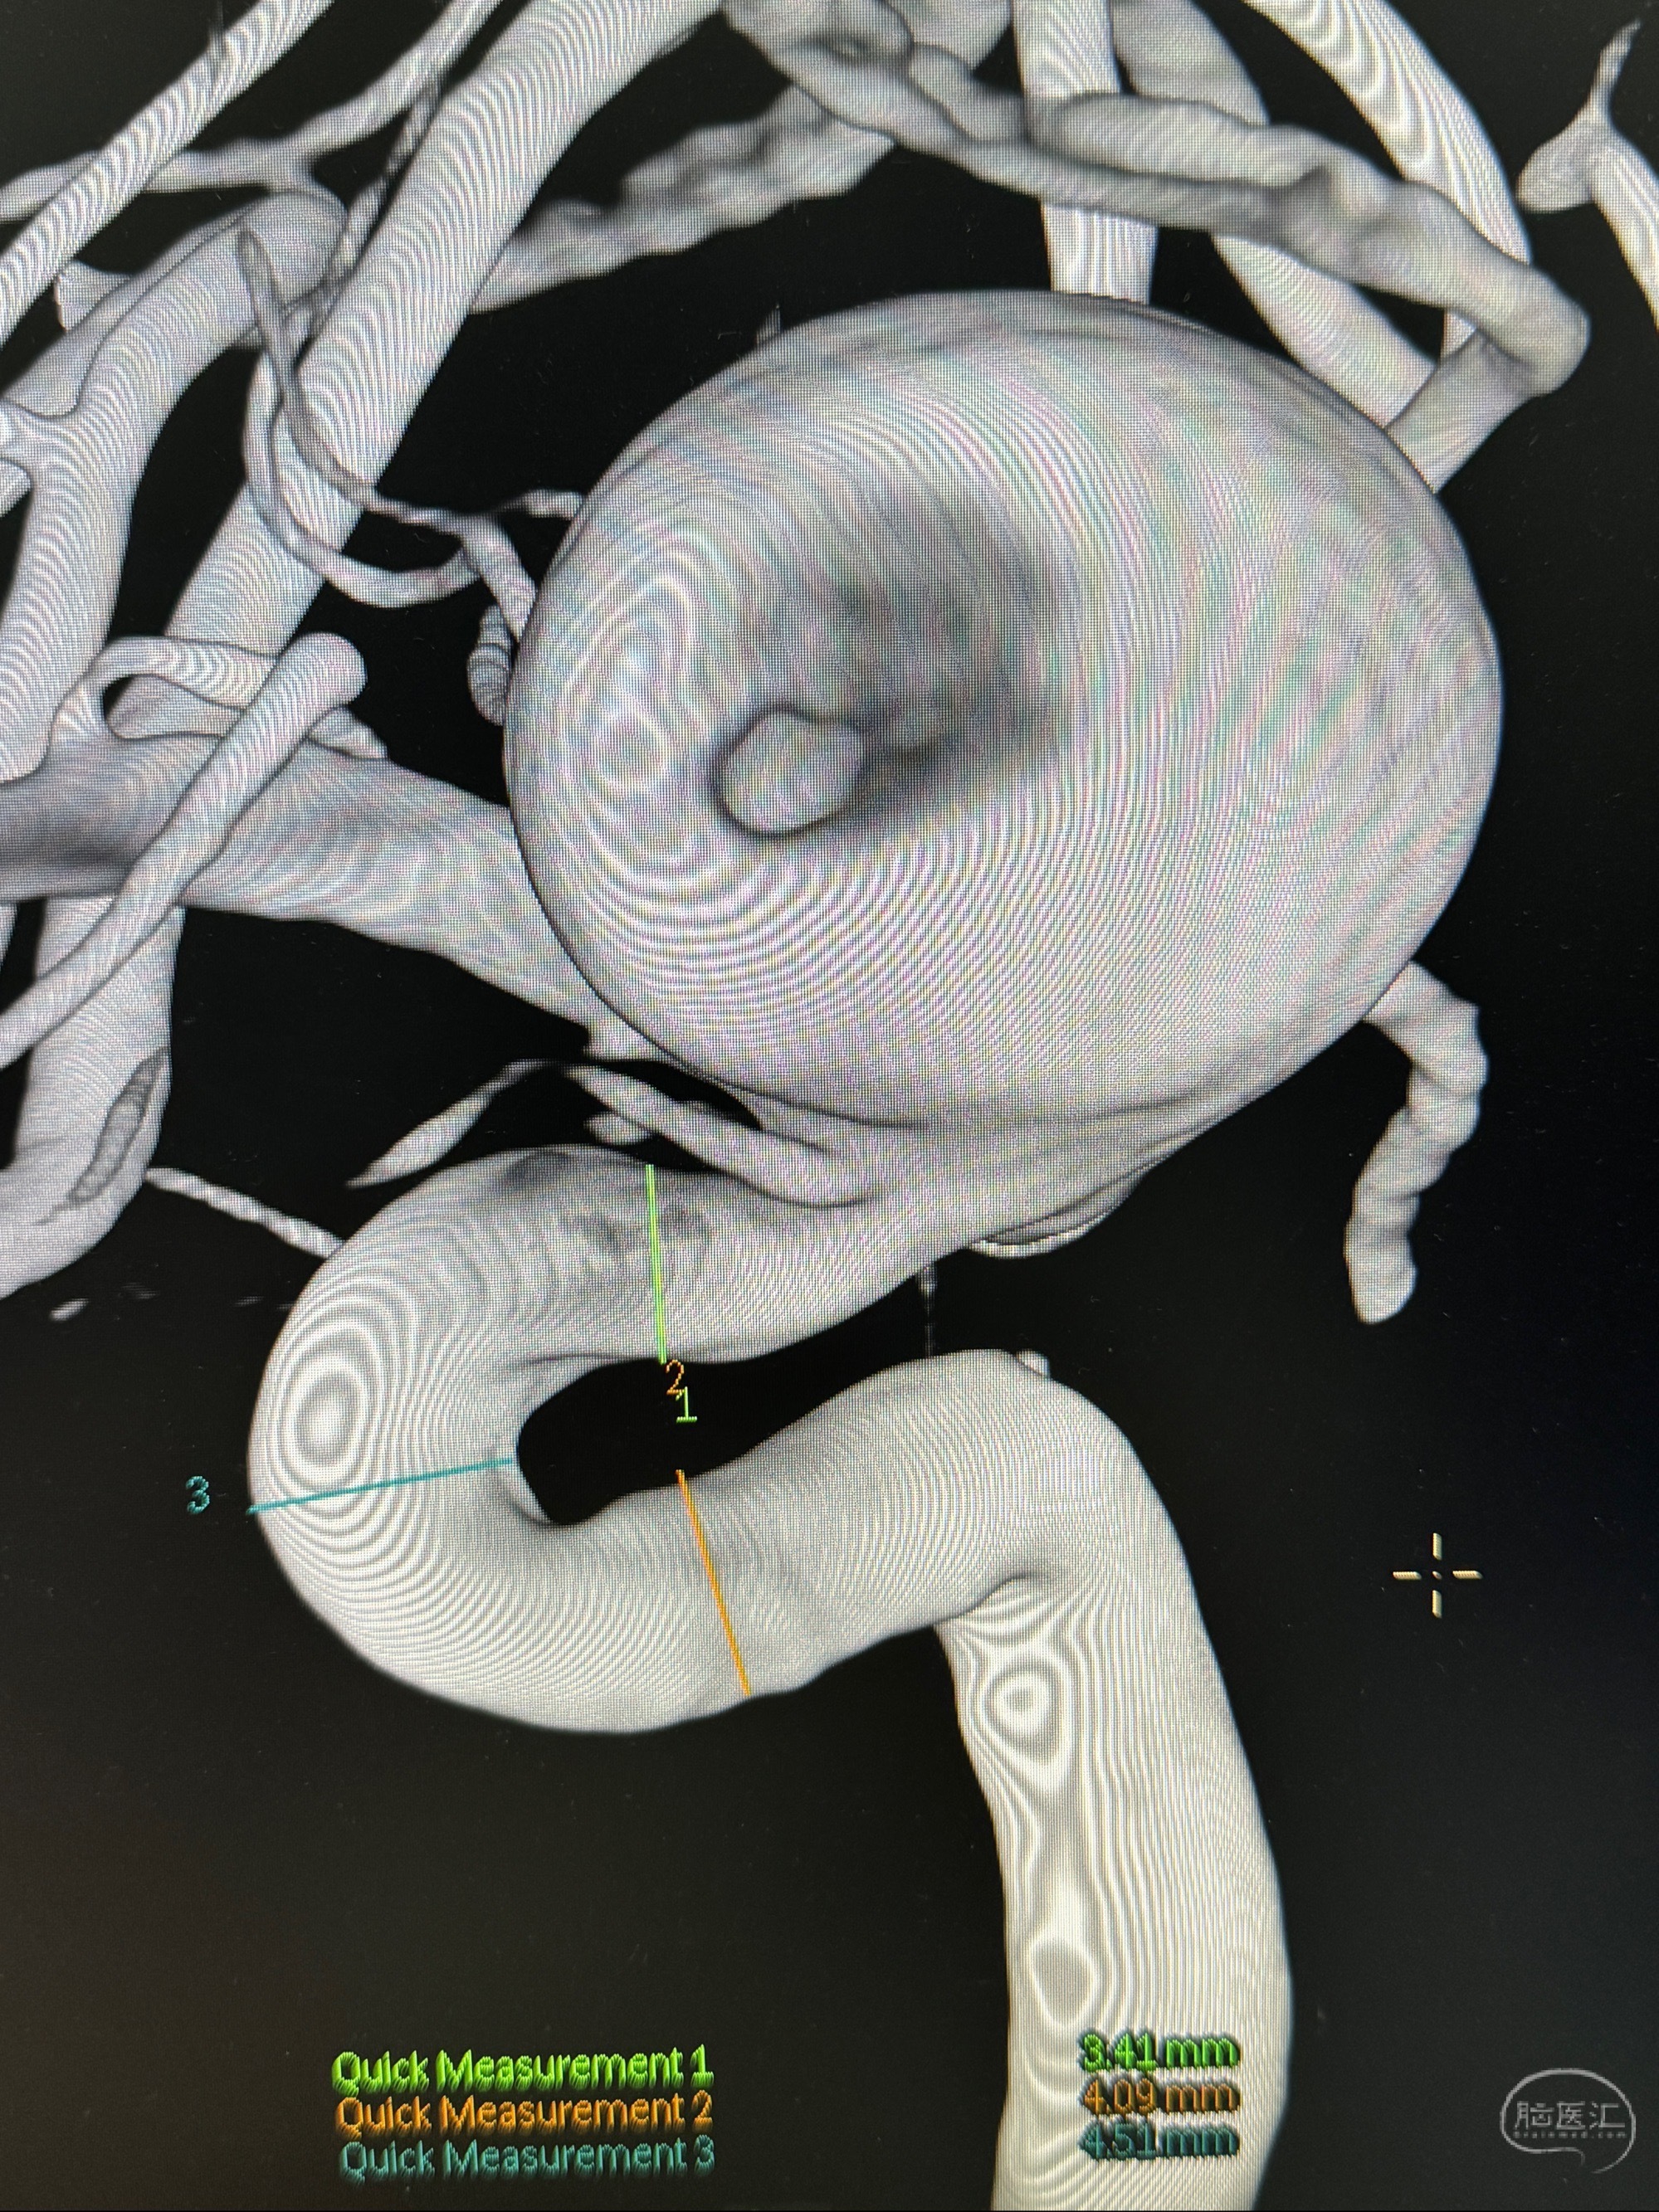

旋转3D展示动脉瘤局部的血管构筑

测量动脉瘤的大小:16*13.8*7.6mm大小,较原先变大,考虑双抗后瘤内血栓溶解可能

观察动脉瘤腔内的血流动力学情况